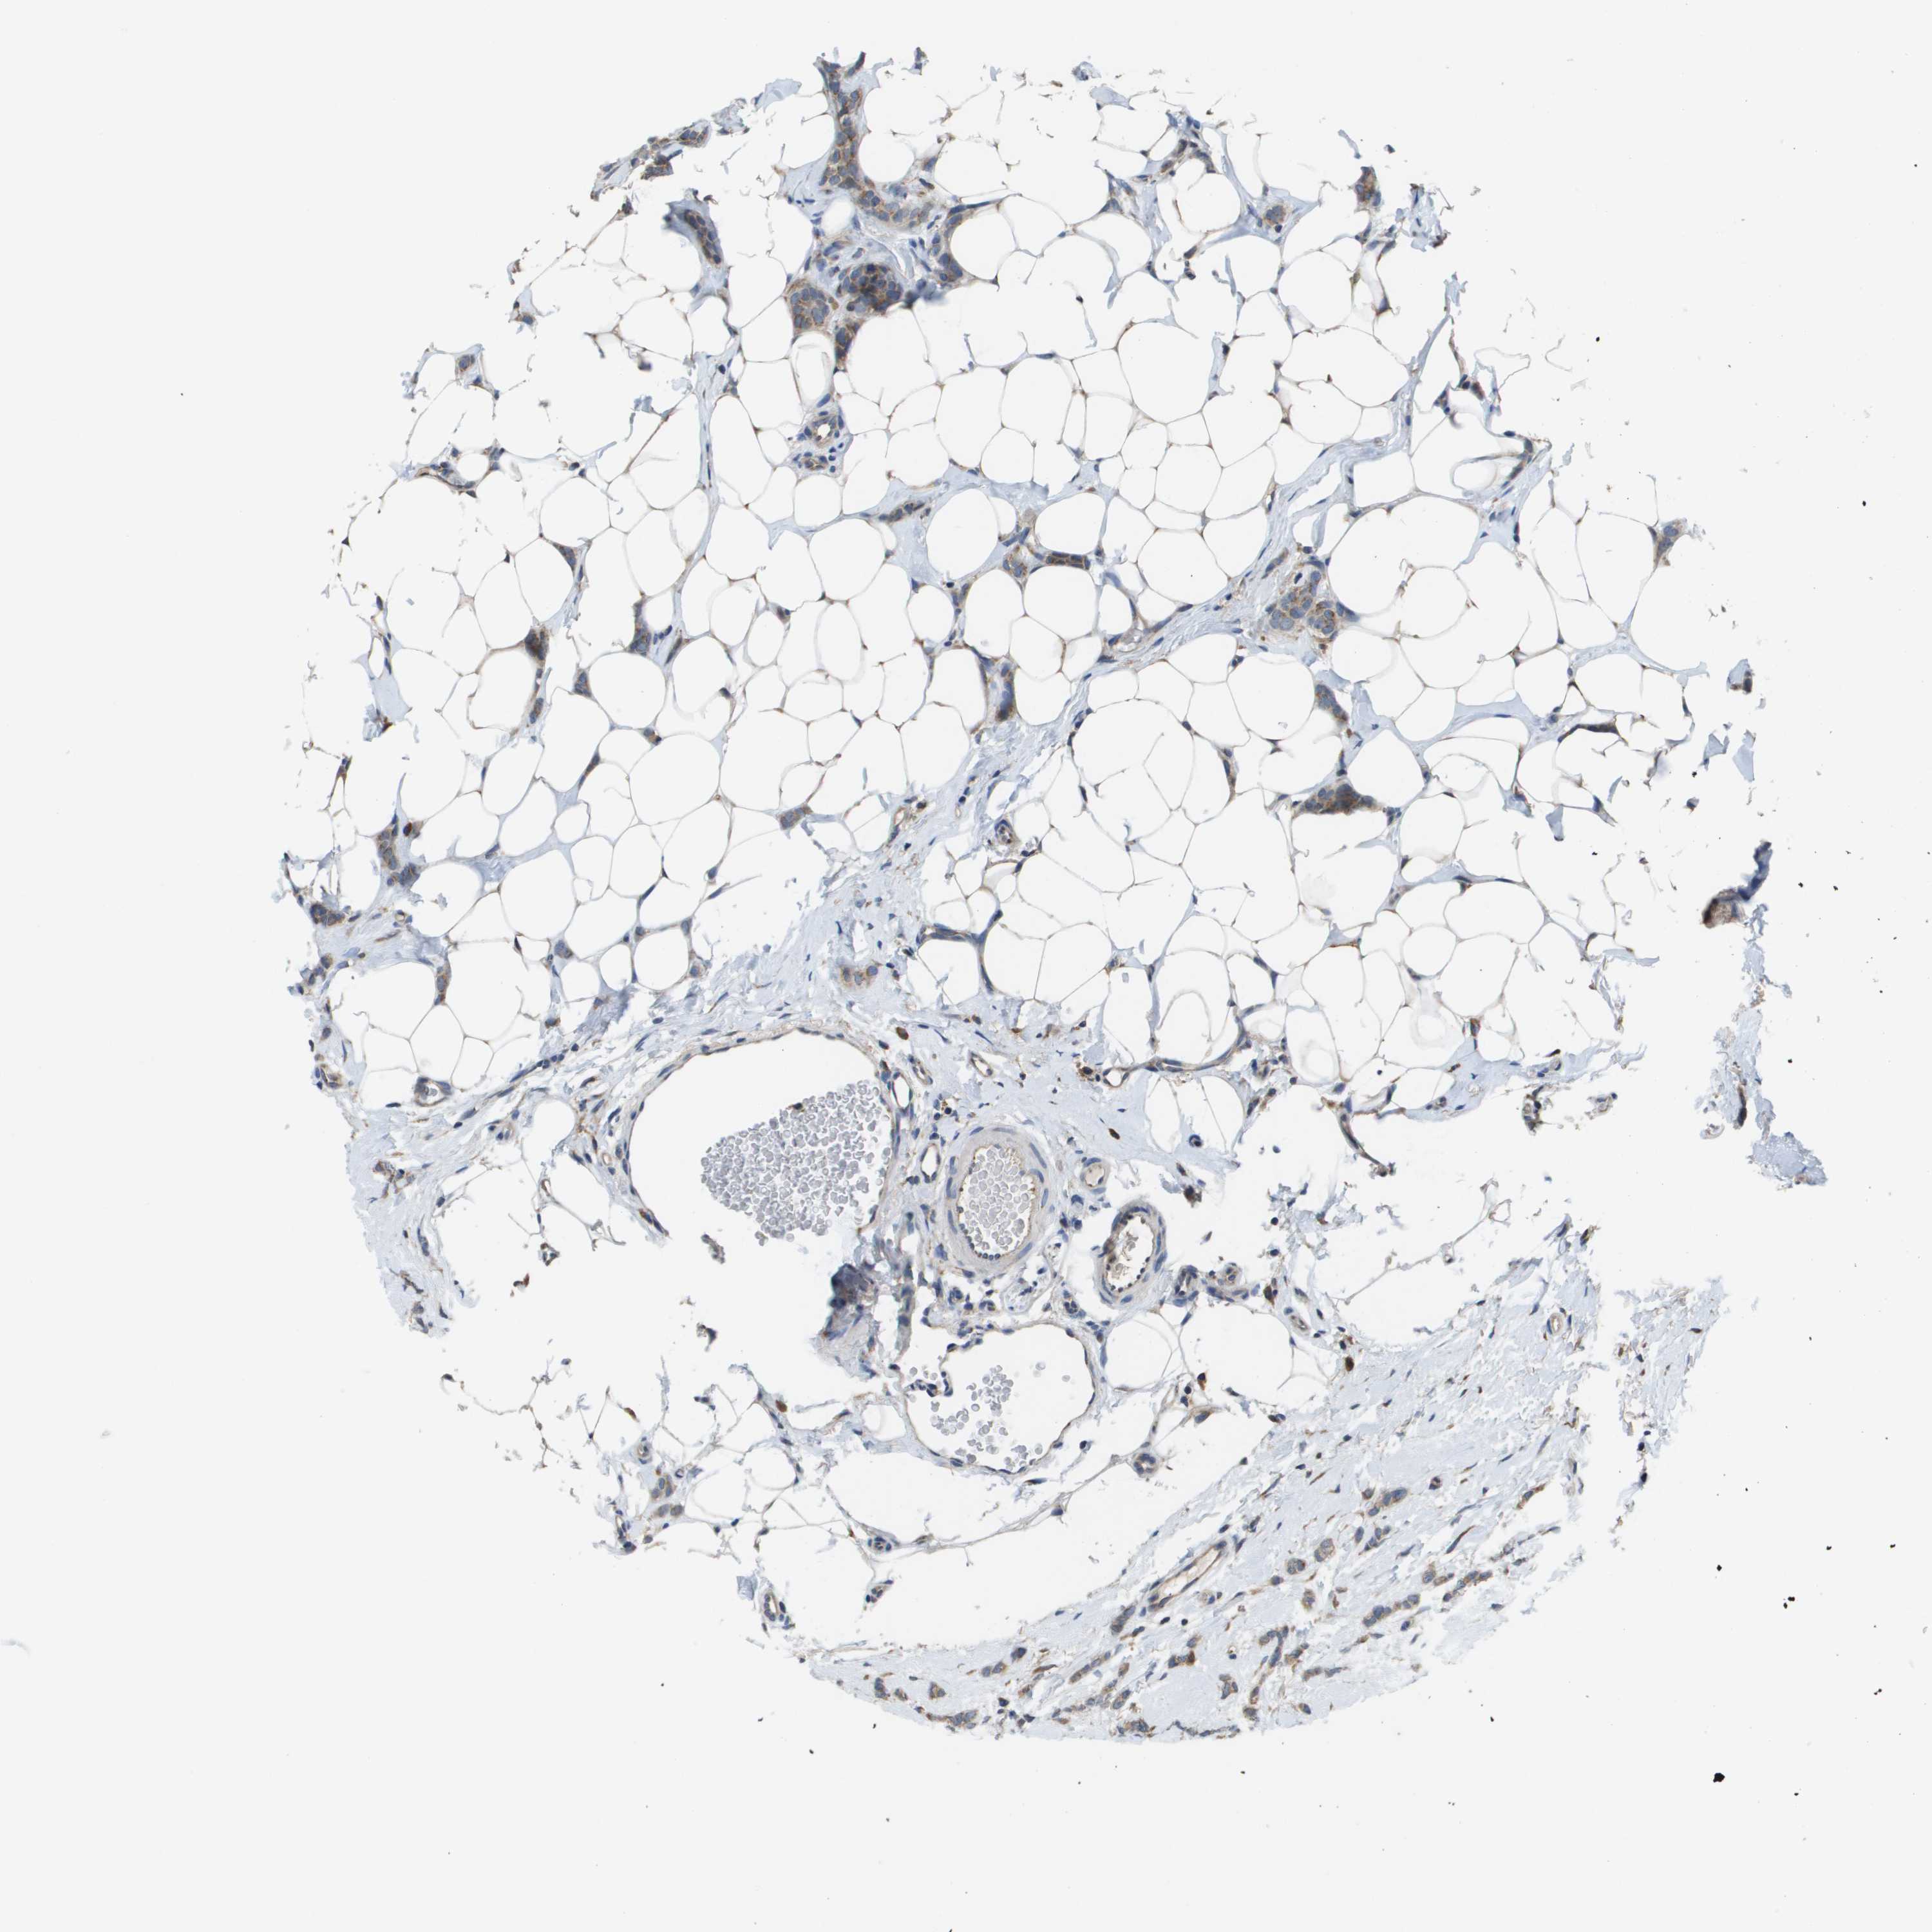

CANCER BREAST CANCER Show tissue menu

BRCA TCGA BRCA VALIDATION PROTEIN EXPRESSION